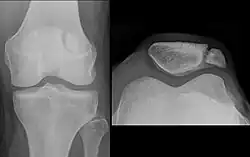

The patella can break in various ways depending on the way it is injured, and into two or more pieces.[1] Types include transverse, the most common, with one fracture line;[5] marginal; osteochondral; and the rare vertical type, or stellate, where a direct compression force gives rise to a comminuted pattern.[5][7] Patella fractures can be further classified as displaced, where the broken ends of bone do not line up correctly and separate by more than 2mm, or undisplaced and stable where pieces of bone remain in contact with each other.[1][7] If fragments of patella bone stick out from the skin it is known as an open patella fracture, and closed if the overlying skin is intact.[1]

Transverse fracture of patella -

Comminuted fracture of patella -

Osteochondral fracture of patella -

Vertical patella fracture